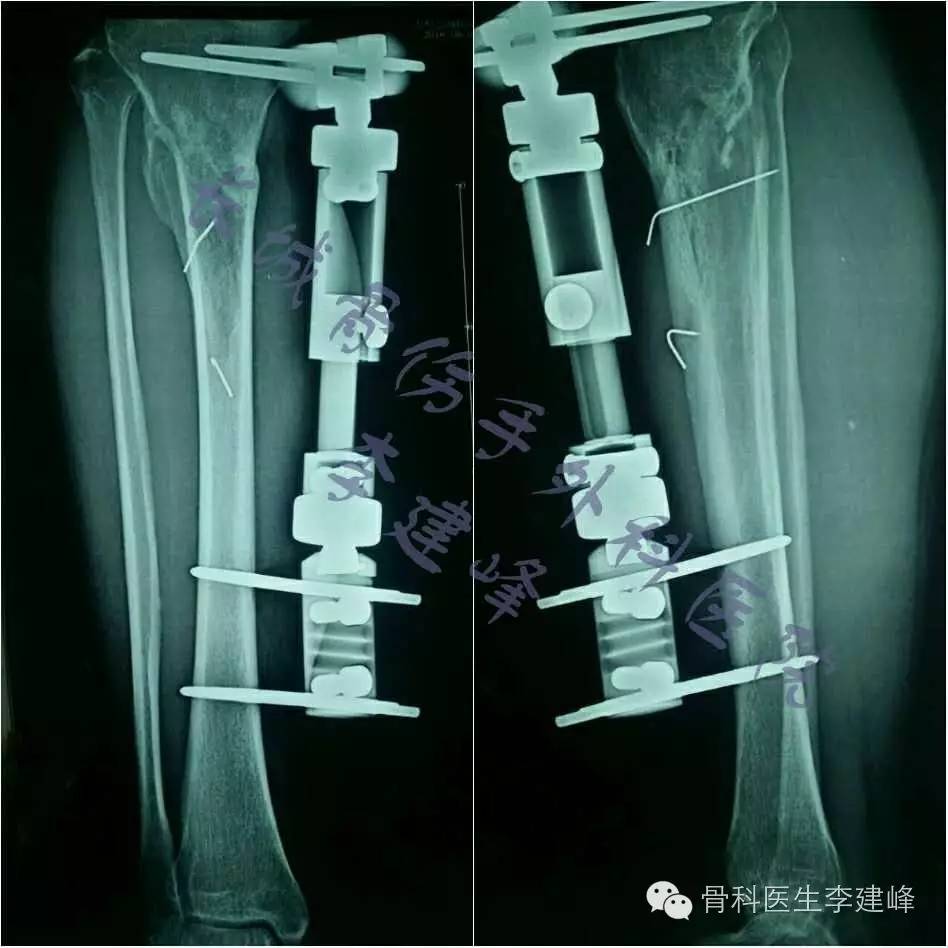

胫腓骨开放骨折外固定支架治疗一例 病例中心 诊疗助手 爱爱医医学网

胫骨开放性粉碎性骨折 经皮钳夹复位 Lcp终极外固定